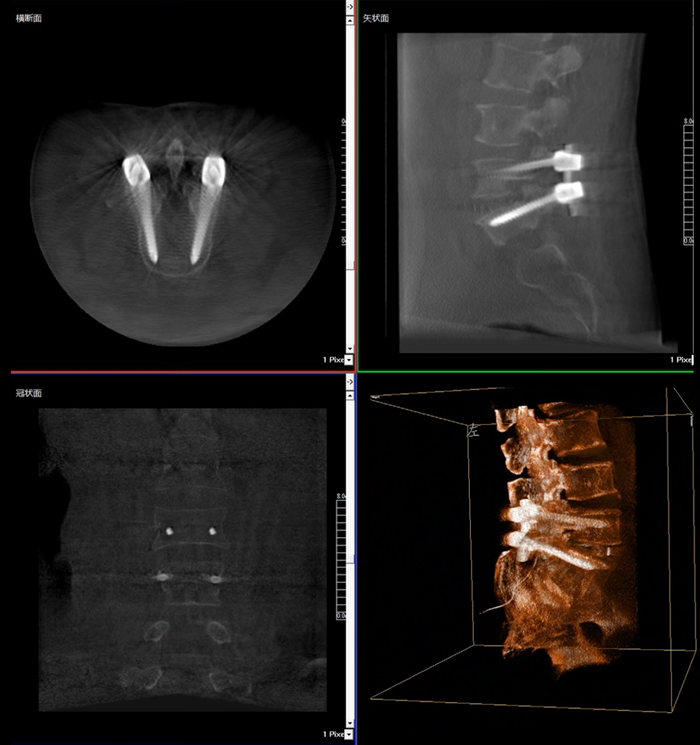

移動式三維C形臂,又稱骨科三維C臂,就是將傳統二維與“類CT模式”相結合的升級版C形臂,能在術中快速地生成橫斷面、矢狀面、冠狀面斷層圖像和三維立體圖像。通過不同方位的斷層圖像,能夠更清晰、完整地顯示椎體及其附件的解剖學結果,直觀地分析病變與周圍組織的立體空間關系,三維斷層成像能夠使手術模擬和手術方案的制定更加準確。

而三維影像的MPR圖像組可以通過不同平面的切分,使成像區內更豐富的信息得以呈現。尤其是二維影像無法涉及的橫斷面,提供了另一個空間維度的信息量。

在MPR圖像中,冠狀面、矢狀面和橫斷面的信息大大提高了醫生對于病灶區以及手術效果的判定。